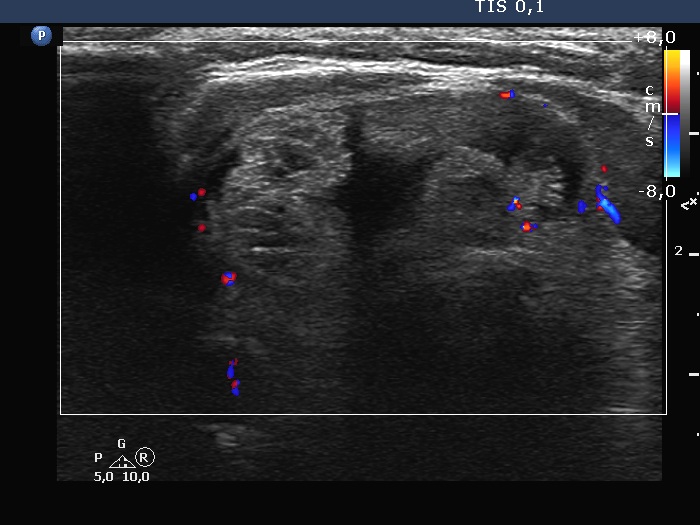

Right lobe, longitudinal scan

Isthmus, transverse scan, color Doppler mode. The vascularity is scanty.